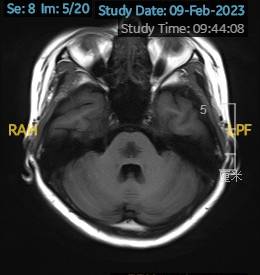

2023.02.09颅脑MR平扫示双侧基底节区及桥脑异常信号,考虑渗透性神经脱髓鞘综合征可能,脑桥部病灶较前范围增大,请结合临床,见图2。

图2 2023.02.09颅脑MR成像示双侧基底节区及桥脑见对称性片样长T1长T2信号,FLAIR呈高信号,较2023-01-18MR所示脑桥病灶范围增大。脑室、脑池、脑沟、脑裂未见明显异常。中线结构居中。